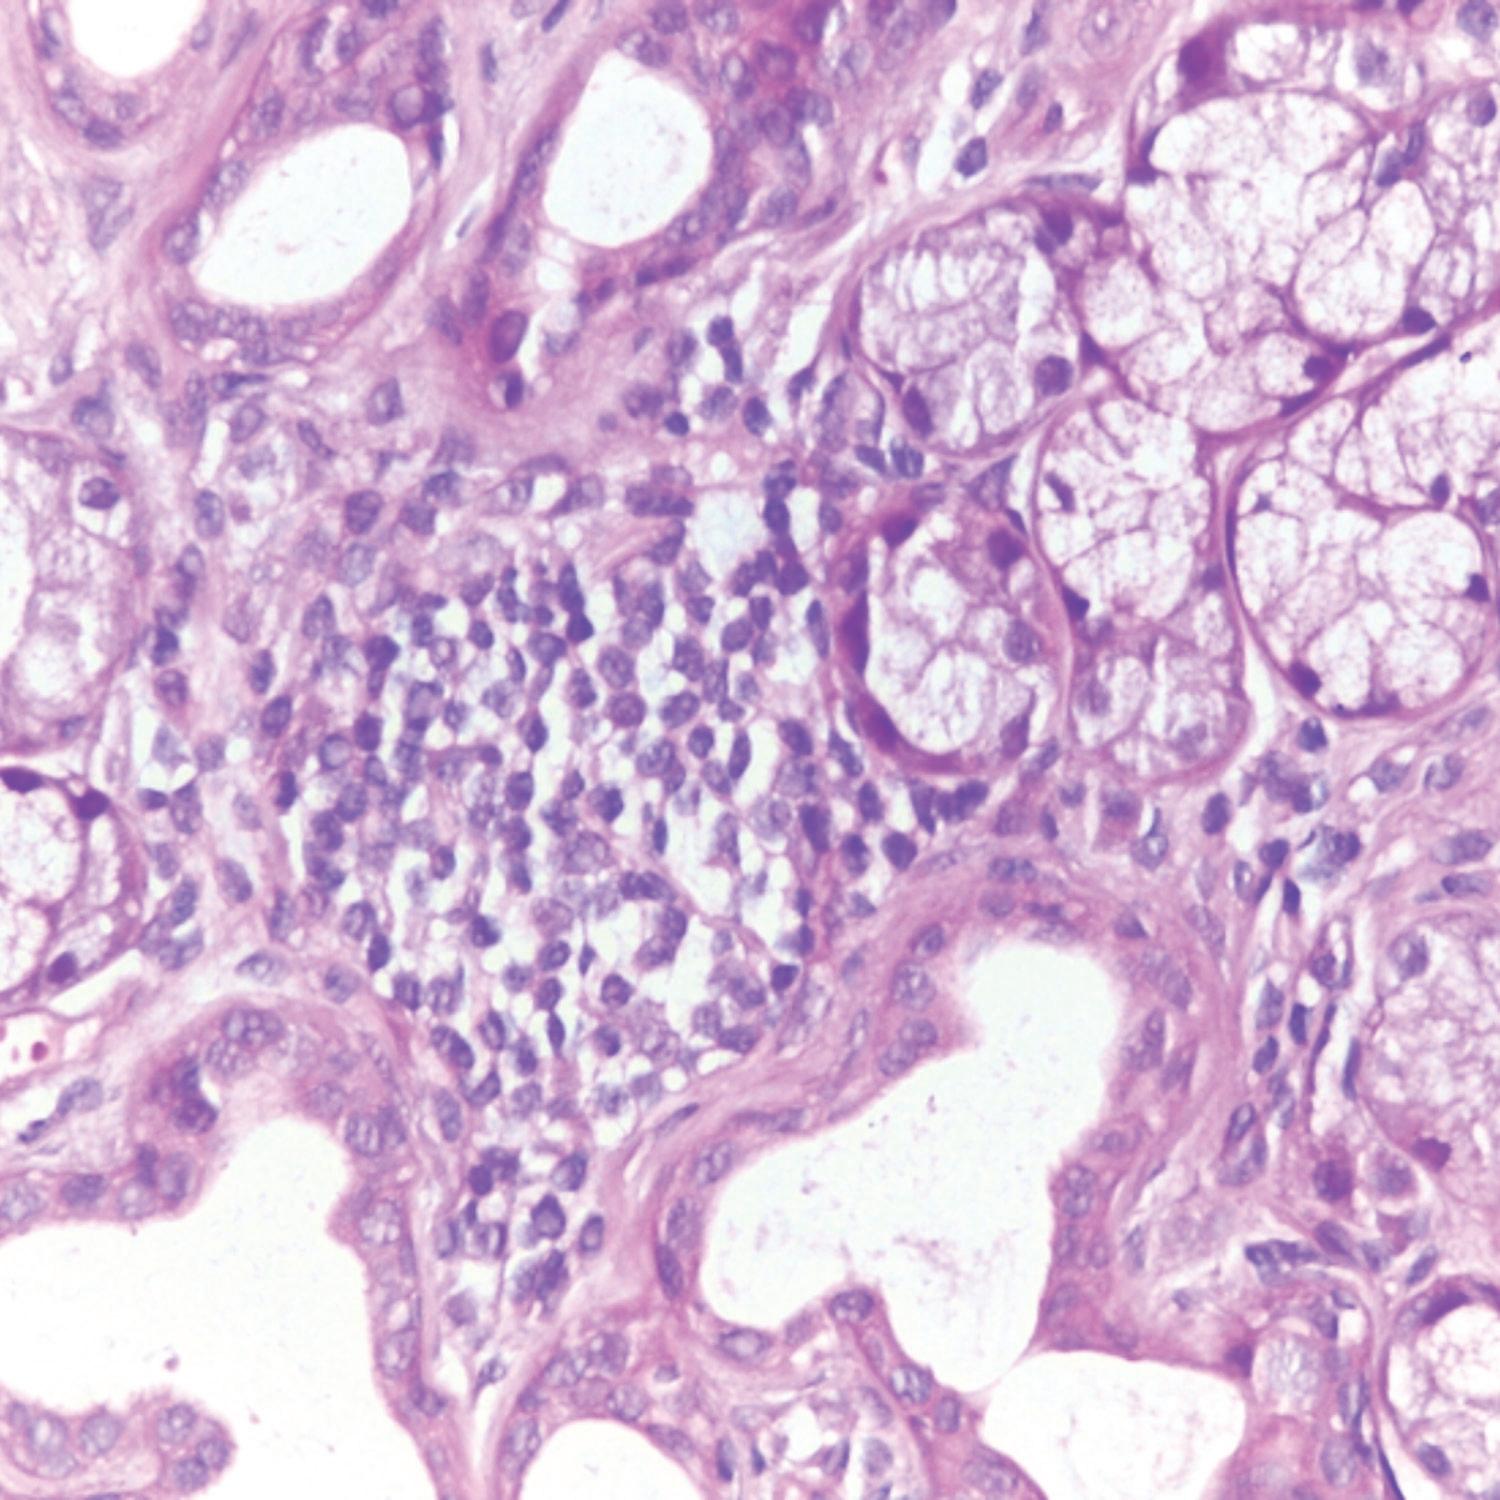

A clinical guide to oral manifestations and diagnosis of limited systemic sclerosis: a case report

Rare angiofibrolipoma of the oral cavity: a case report